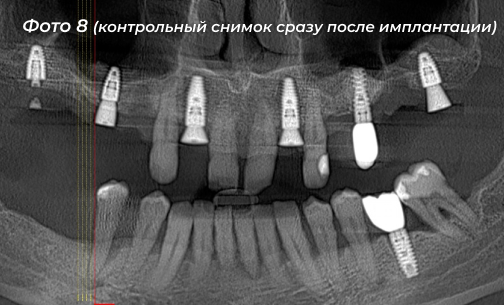

Было установлено 5 имплантов на верхней челюсти, 6-ой имплант был установлен ранее  (Фото 7, 8). Сразу дать нагрузку на импланты не решились в связи с тем, что костная ткань у пациента была рыхлая.